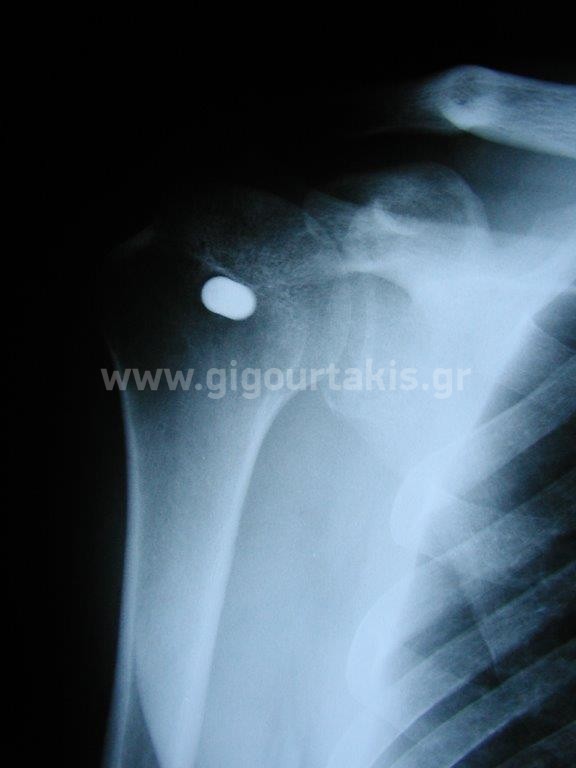

ΔΙΑΤΟΜΗ ΜΑΚΡΑΣ ΚΕΦΑΛΗΣ ΔΙΚΕΦΑΛΟΥ ΧΕΙΡΟΥΡΓΙΚΗ ΑΠΟΚΑΤΑΣΤΑΣΗ ΠΕΡΙΣΤΑΤΙΚΟ 1 01.ΑΚΤΙΝΟΓΡΑΦΙΑ 2. 03. 04.ΑΡΧΙΚΗ ΚΑΜΨΗ ΩΜΟΥ 05. ΑΡΧΙΚΗ ΑΠΑΓΩΓΗ ΩΜΟΥ 06.ΕΝΕΡΓΗΤΙΚΗ ΚΑΜΨΗ ΑΓΚΩΝΟΣ 07.ΑΡΧΙΚΗ ΕΞΩ ΣΤΡΟΦΗ ΩΜΟΥ 08.ΤΕΛΙΚΗ ΚΑΜΨΗ ΩΜΟΥ 09.ΤΕΛΙΚΗ ΑΠΑΓΩΓΗ ΩΜΟΥ 10.ΤΕΛΙΚΗ ΟΠΙΣΘΙΑ ΠΡΟΣΑΓΩΓΗ ΩΜΟΥ 11.ΤΕΛΙΚΗ ΕΞΩ ΣΤΡΟΦΗ ΩΜΟΥ 12.ΤΕΛΙΚΗ ΕΣΩ ΣΤΡΟΦΗ ΩΜΟΥ Στις κατηγορίες:ΑΝΩ ΑΚΡΟ, ΩΜΙΚΗ ΖΩΝΗ ΒΡΑΧΙΟΝΙΟ, ΔΙΑΤΟΜΗ ΜΑΚΡΑΣ ΚΕΦΑΛΗΣ ΔΙΚΕΦΑΛΟΥ-ΧΕΙΡΟΥΡΓΙΚΗ ΑΠΟΚΑΤΑΣΤΑΣΗ